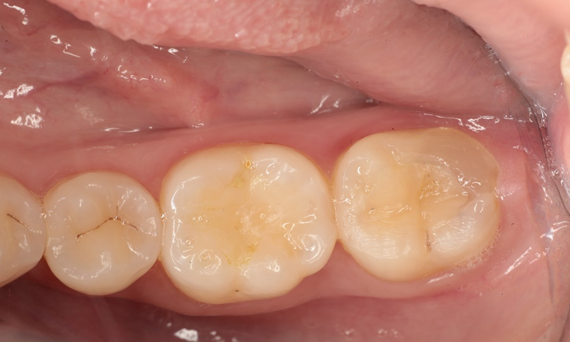

Before: Pre-operative clinical scenario after endodontic therapy.

After: 1 month after the CEREC Tessera onlay was bonded.

A 20-year-old female patient had endodontic treatment of her lower right 2nd molar. A chairside onlay was fabricated from the new high-strength ceramic CEREC Tessera ALD.